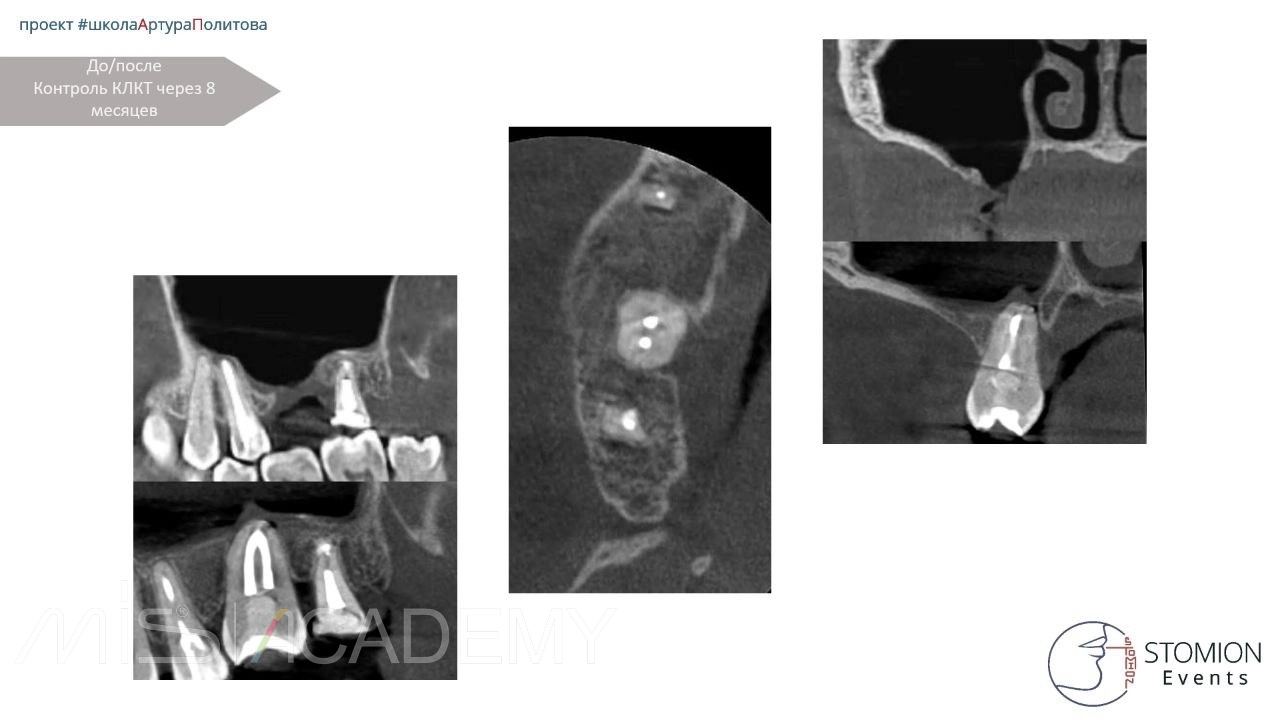

• Контрольное КЛКТ.

• Через 6 месяцев — контрольное КЛКТ и осмотр.

• Исход положительный, костная регенерация и интеграция трансплантата.